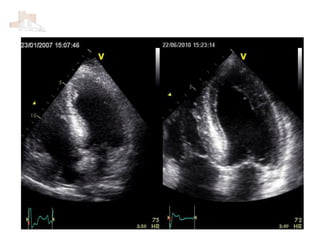

 19 años, trasplante hepático por atresia de vías biliares.

 Hiperactividad

 Tto. con tacrolimus.

 AF: madre F.A./flutter, coartación Ao, ICFEP; Hermana VAB, hepatitis

autoinmune.

 Disnea de esfuerzos moderados desde hace 1,5 meses.

Dur Ami 123 ms Dur Ar 160 ms

PSP 50 mmHg

E/E’12,5 E/E’ 7,7